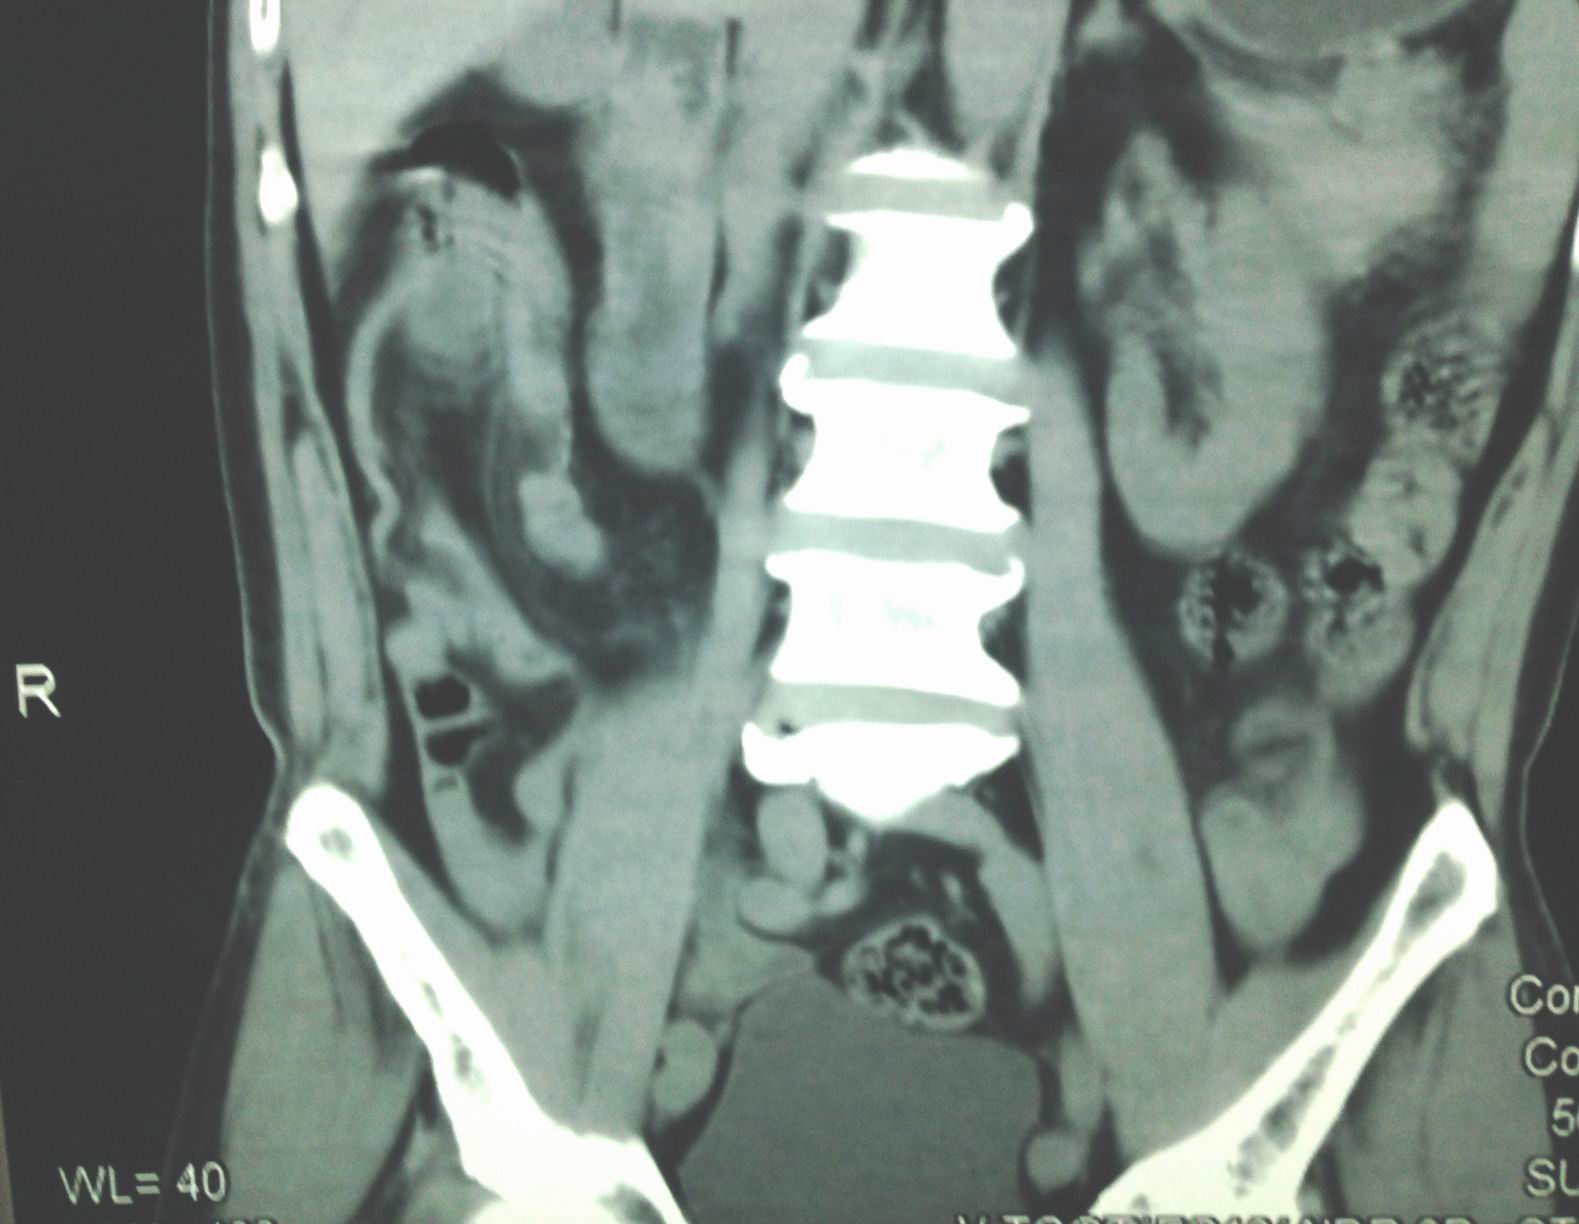

CT scan abdomen detected right colon moving up with coecum intussusception (CT1 frontal section;, CT2, sagital section;CT3, frontal section).

Emergency operation with diagnosis colo-colic intussusception by appendicular mucocele.